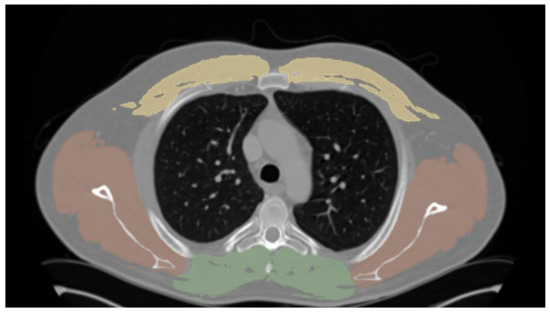

Mediastinal fat was semi-automatically assessed by outlining the mediastinal fat using a CT-attenuation threshold between −195 and −15 HU (Figure 2).

Figure 2. Morphometric measurements of anterior mediastinal fat on (a) axial and (b) sagittal reformations.